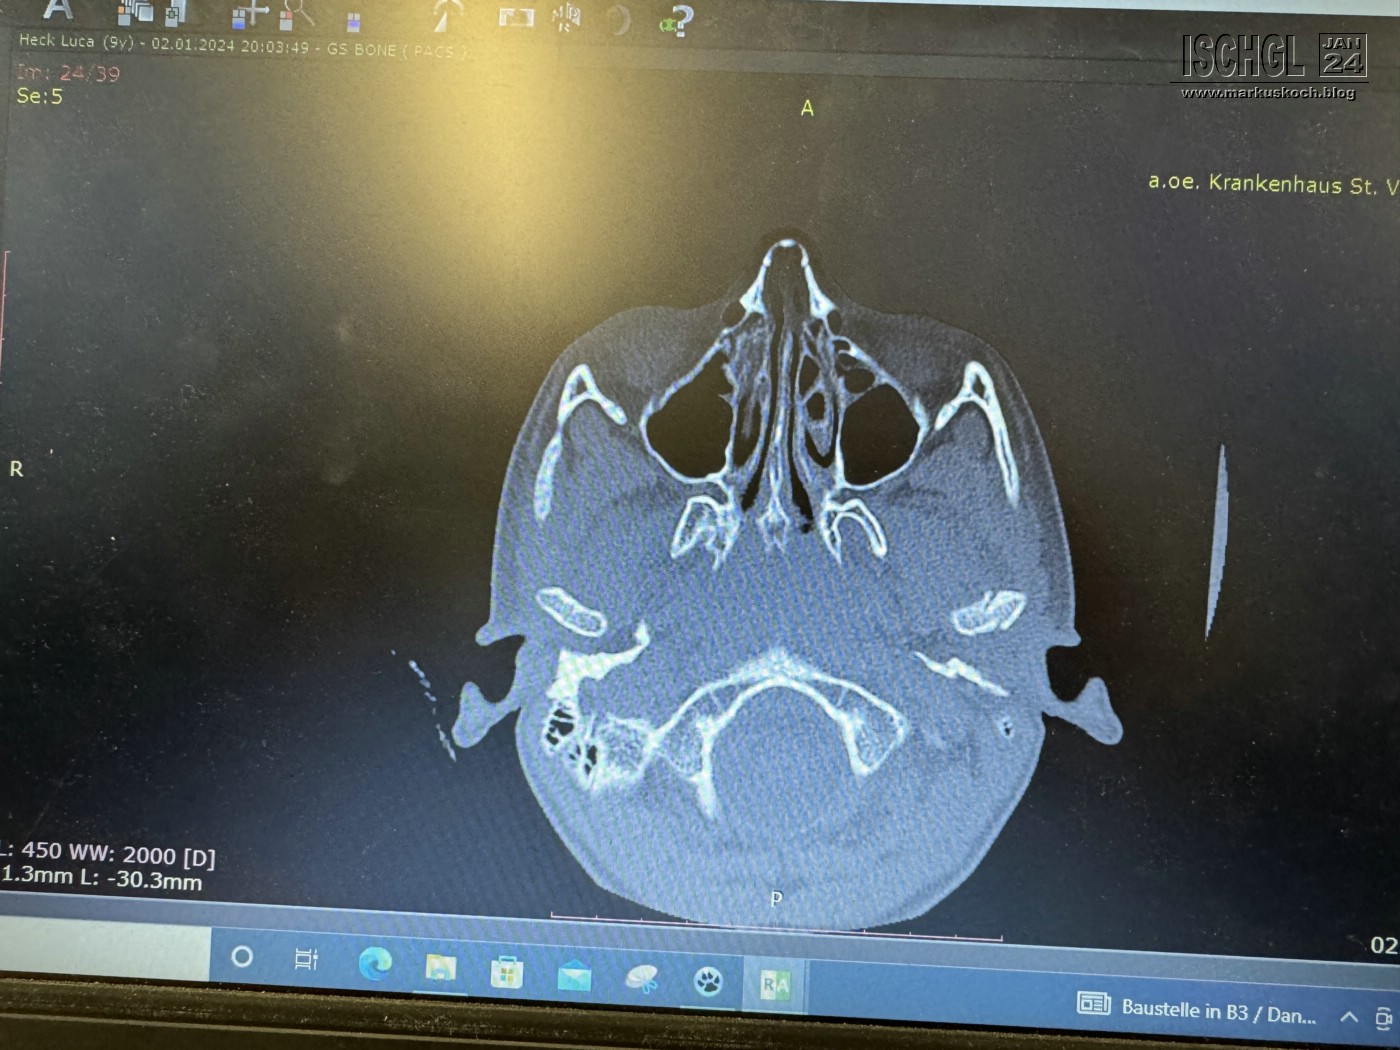

Leider ist Luca auf der Eislauffläche bzw. am nicht präparierten Rand beim Bremsen aufs Kinn gefallen. Anschließend Arzt in Ischgl und weil er nicht so exakt am Kopf röntgen konnte, sollten wir nach Zams ins Krankenhaus. Dort wurde dann genau nachgeschaut und sogar ein CT gemacht. Leider hat sich herausgestellt, dass er sich das Gelenkköpfchen des Unterkiefers gebrochen hat.

Daher reisten wir direkt am Mittwoch früh ab und daheim gleich in die Uniklinik Frankfurt, wo überlegt & entschieden werden sollte, ob es operiert werden soll.

Die Entscheidung fiel dann erst am Donnerstag früh mit dem Rat zu einer OP & einer Schraube, damit es keine Fehlbildungen im Wachstum geben soll.

Der arme Kerl wurde dann am MO, 8.1. erfolgreich operiert. ☹ Aber das wird wieder. 😊